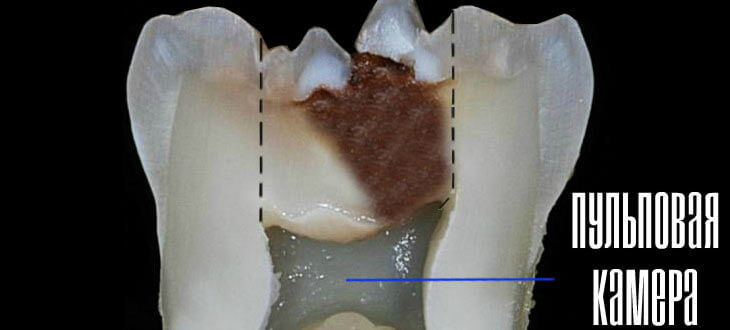

- Деструктуризация — результат заражения пульповой камеры причинного зуба анаэробными бактериями и токсинами, которые они выделяют. Проникновение наблюдается через кариозные полости, связанные с пульповой камерой или через дентинные трубочки твердых тканей дентина. В некоторых случаях инфекция попадает сквозь пародонтальный карман, проникает с кровотоком, если присутствует инфекционное заболевание (гайморит, остеомиелит).

При хроническом гангренозном пульпите симптомы зависят от состояния зубной полости. Блокировка пульповой камеры приводит к долго не проходящим ноющим болям, возникающим из-за скопления гнойного экссудата. Чаще пульпа полностью вскрыта, что делает возможным свободный отток экссудата. Лимфоузлы немного увеличены и имеют слабую болевую реакцию при пальпации.

- Визуальный осмотр выявляет разрушение коронки больного зуба, обширную кариозную полость, типичный серый оттенок зуба. Постукивание (перкуссия) и пальпация выявляет небольшую чувствительность. Иногда осмотр указывает на увеличение периодонтальной щели, альтерацию костной ткани в районе зубного корня.